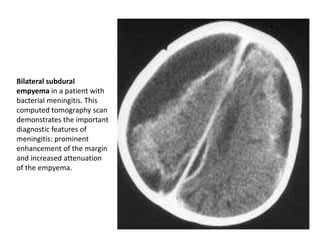

Bilateral subdural

empyema in a patient with

bacterial meningitis. This

computed tomography scan

demonstrates the important

diagnostic features of

meningitis: prominent

enhancement of the margin

and increased attenuation

of the empyema.